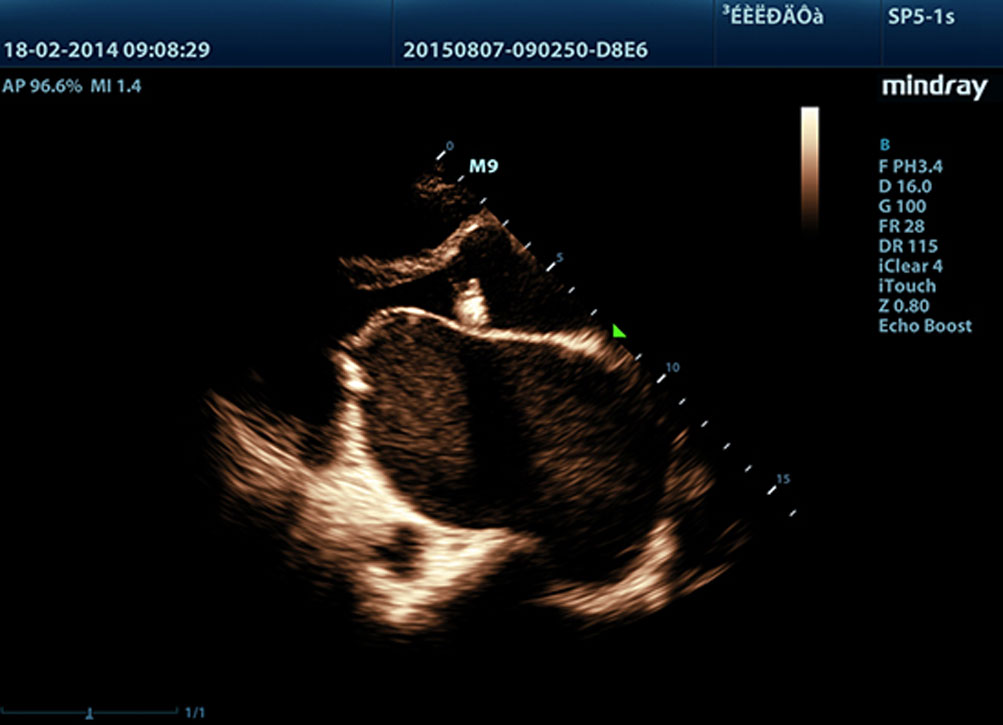

Single Crystal ile 3T Prob Teknolojisi Tek Kristalli

Daha belirgin g?rĂŒntĂŒler sa?layan, M9 ile uyumlu tĂŒm problar Mindray'in benzersiz 3T prob teknolojisiyle teslim edilir. Single crystal teknolojisinin eklenmesiyle gĂŒcĂŒ artan M9, ?zellikle zorlu hasta taramas? s?ras?nda daha iyi penetrasyon ve dinamik renk ak??? olana?? sunar.